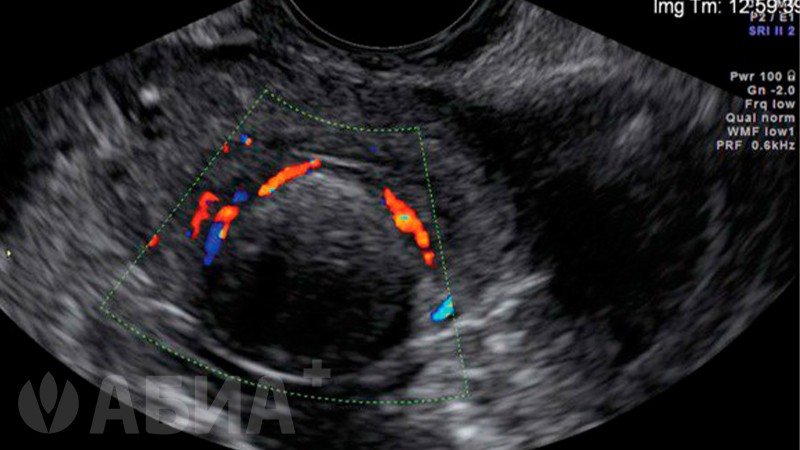

• УЗИ малого таза девочкам трансабдоминальным датчиком через переднюю брюшную стенку

УЗИ органов малого таза 1 датчиком 2600